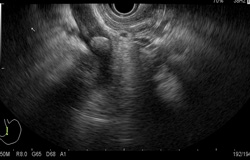

Endoscopic ultrasound (EUS) is an advanced endoscopic procedure specialized for the evaluation of various benign and malignant diseases involving the gastrointestinal tract and pancreatobiliary system using an ultrasound probe equipped on a flexible endoscope. Depending on the disease condition being evaluated, an EUS procedure usually takes about 20 to 40 minutes. Common conditions that can benefit from EUS are listed below (Table 1).

- Common bile duct (CBD) stone

- Abnormal liver function tests or obstructive jaundice